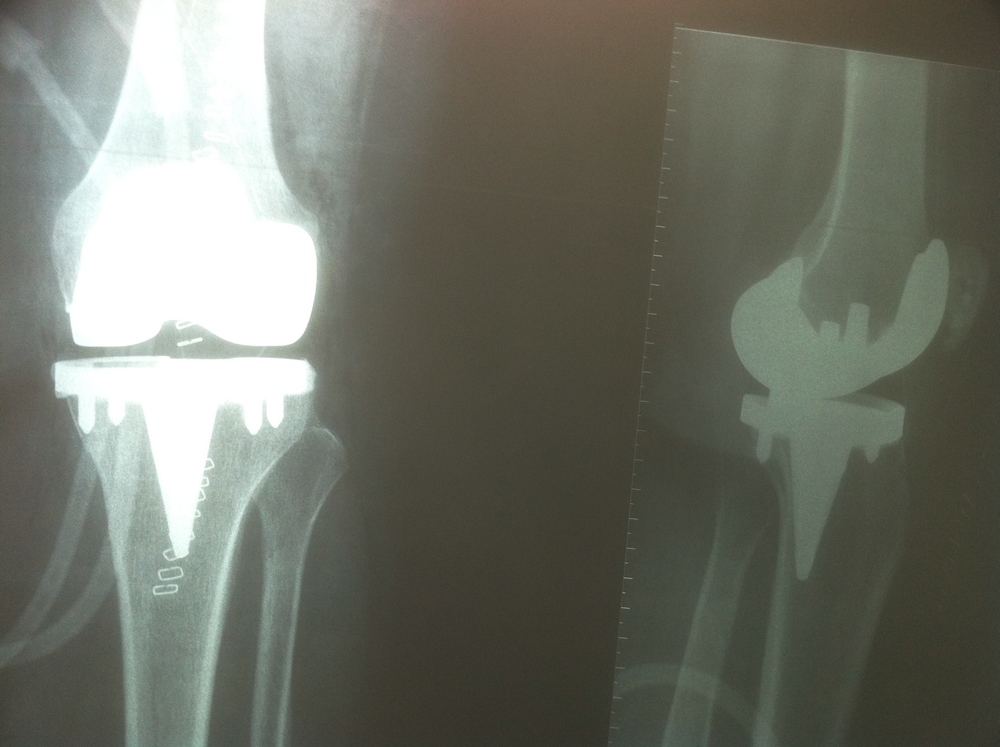

Dans ce propos, nous allons tâcher d’éclairer le lecteur sur la nature des implants utilisés en chirurgie orthopédique pour réaliser les prothèses articulaires (hanche, genou, épaule, coude, cheville, articulations des doigts…). Les termes prothèses articulaires et arthroplasties sont interchangeables même si une nuance puriste peut exister. Le but d’une prothèse articulaire est de remplacer une articulation détruite suite à l’usure liée à l’âge, une infection, une tumeur ou un traumatisme par des implants inertes destinés à restaurer la fonction. On précisera cependant qu’il ne s’agit pas ici de prothèses – appareillages destinées à remplacer un membre amputé.

Actuellement, l’amélioration de la qualité des matériaux ainsi que de leur usinage, surtout le polissage de la surface de friction, ont permis de porter la durée de vie des prothèses au-delà de 30 ans. Trois catégories de matériaux sont actuellement utilisées. Il s’agit des alliages métalliques, des céramiques et du polyéthylène de haute densité. Des essais d’implants en carbone sont en cours.

Les alliages métalliques sont essentiellement en chrome – cobalt et en titane. Les céramiques sont des matériaux non métalliques et non organiques obtenus par l’effet de fortes températures sur de l’alumine ou du zircon. Le polyéthylène est un matériau plastique issu de l’industrie pétrochimique. Il sert à constituer la surface de friction des implants. L’introduction du ciment acrylique dans la fixation des implants à l’os date du début des années 60. Depuis le milieu des années 80, le concept de prothèse sans ciment est apparu. Le principe consiste à recouvrir la surface de contact des implants avec l’os d’un revêtement dit ostéo-conducteur. Il s’agit de l’hydroxyapatite, un composant minéral naturel de l’os que l’on produit artificiellement. Au contact de la prothèse, l’os du voisinage identifie cet hydroxyapatite comme un de ses propres constituants et le colonise. La prothèse devient ainsi intégrée à l’os. On parle alors de stabilité secondaire. Naturellement, en attendant cette repousse d’os sur le revêtement d’hydroxyapatite, la stabilité primaire est assurée par l’impaction en force de la prothèse dans l’os et éventuellement fixée par des vis complémentaires. Les couples de friction (surface de frottement des implants) sont de plusieurs sortes : métal – PE, céramique – PE, céramique – céramique. Le couple métal – métal dit de gros diamètre a été utilisé au moins durant trois périodes depuis le 20ème siècle dont la dernière au-début des années 2000 avant d’être à nouveau abandonné pour cause de relargage excessif de particules de métal dans l’organisme.